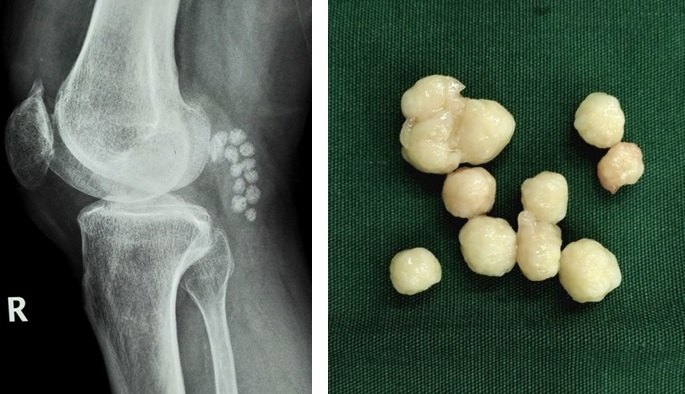

8.对于关节内软骨剥脱形成游离体,以及半月板撕裂产生卡压、交锁症状的患者可以考虑膝关节镜下清理游离体(图8)和增生的滑膜组织,或镜下微创缝合损伤撕裂的半月板(图9)。前(后)交叉韧带断裂的可行关节镜下的韧带重建手术(图10)。

图8.膝关节镜清理游离体